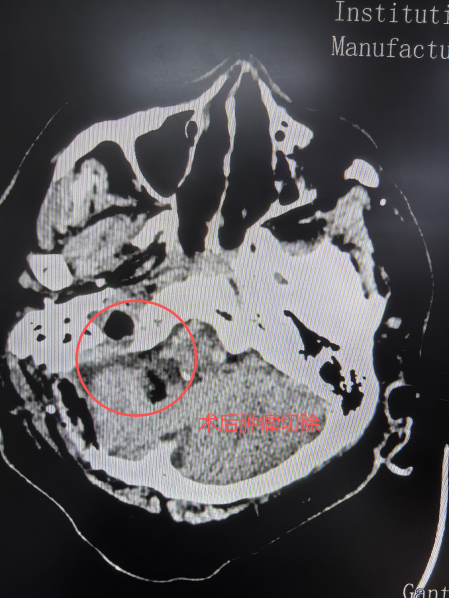

70岁的那买提(化名)被间断性头痛困扰8个月之久,在当地医院检查发现右侧桥小脑角区占位伴内通道骨折破坏。由于家庭经济条件有限,一直未能接受手术治疗。近期,老人突发听力下降、头晕及四肢乏力,紧急于喀什地区第一人民医院就诊,急查CT检查显示,他的右侧桥小脑角区占位性病变,引发肿瘤卒中,病情危急。

由于患者合并患有高血压、糖尿病、冠心病心脏起搏器植入等多种基础病,无法进行磁共振检查。其肿瘤体积比较大,累及椎基底动脉、脑干,与面神经、听神经、舌咽神经等多条神经,内听道骨质也有损坏,手术难度与风险极高。